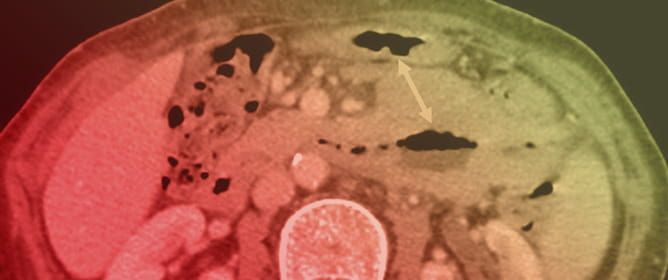

Primary Small Bowel MALT Lymphoma with Concurrent Pulmonary Dissemination: A Case Report

Marginal zone lymphomas (MZLs) are indolent mature B-cell neoplasms. Approximately 3.4% of gastrointestinal mucosa-associated lymphoid tissue (MALT) lymphomas involve the small bowel. Pseudoaneurysmal dilation has been reported in up to 35% of patients with small bowel MALT lymphoma. We report the case of a 73-year-old woman with ulcerative colitis in remission who presented with hematuria, constitutional symptoms, and progressive respiratory distress. Imaging incidentally revealed pseudoaneurysmal dilation of the small bowel and thoracic findings suggestive of pulmonary lymphangitic dissemination. A PET scan showed lung, nodal, and small bowel infiltration. Histopathological and flow cytometry examinations confirmed small bowel MZL, and bone marrow biopsy excluded marrow involvement. The patient was treated with R-CHOP chemotherapy and then R-Bendamustine, achieving complete clinical and radiological remission. This case illustrates a rare presentation of intestinal MALT lymphoma and emphasizes the diagnostic significance of correlating imaging and clinical findings in identifying pseudoaneurysmal dilatation and distinguishing it from other potential causes.